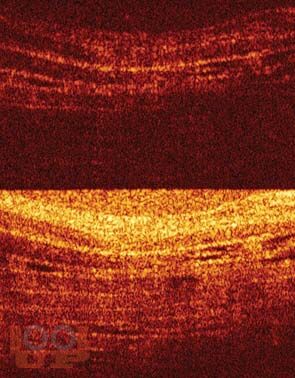

В пособии, наряду с традиционными, представлен универсальный для диагностики заболеваний нижних мочевых путей метод — кроссполяризационная оптическая когерентная томография. На основе патогенетического подхода освещены основные принципы лечения цистита.